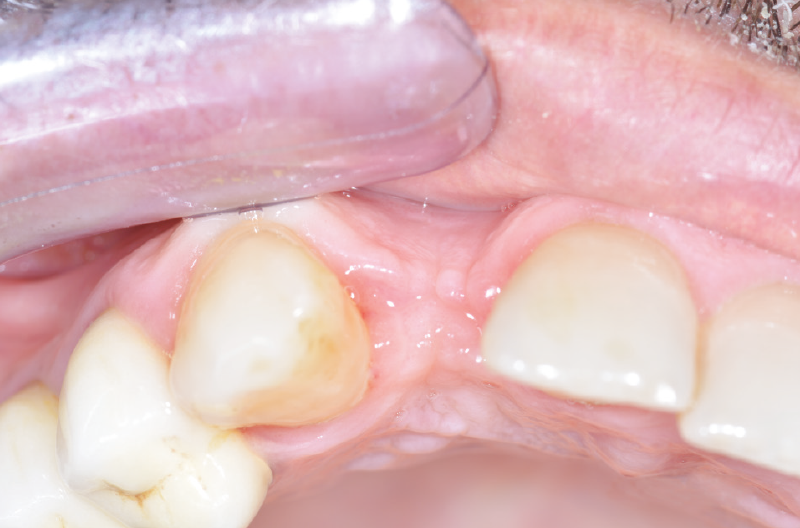

Dopo la maturazione dei tessuti molli all’esame intraorale si nota come la papilla tra dente e impianto sia presente ma non ancora matura, con un piccolo cratere e con un’anatomia inversa nella zona interprossimale (Figg. 50-53).

Fig. 50 – Controllo clinico e radiografico dopo maturazione dei tessuti molli

Fig. 51 – Controllo clinico e radiografico dopo maturazione dei tessuti molli

Fig. 52 – Papilla non ancora matura con anatomia inversa nella zona interprossimale

Fig. 53 – Papilla non ancora matura con anatomia inversa nella zona interprossimale

Ciò rappresenta una situazione sfavorevole non solo per l’estetica ma anche per le manovre di igiene orale domiciliare. Si procede, a questo punto, ad una ulteriore modifica della forma del provvisorio, per dare maggiore spazio ai tessuti molli (Figg. 54-62).